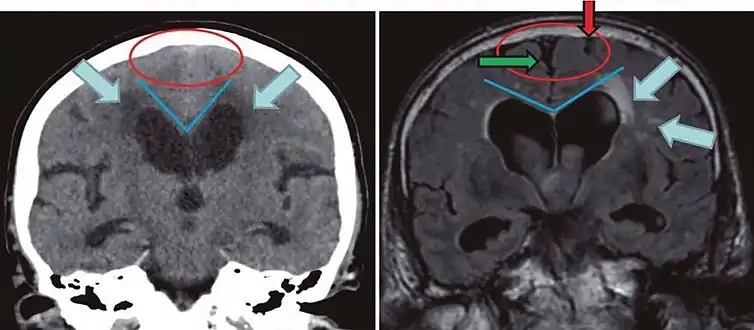

Leukoaraiosis is a particular abnormal change in appearance of white matter near the lateral ventricles. It is often seen in aged individuals, but sometimes in young adults.[1][2] On MRI, leukoaraiosis changes appear as white matter hyperintensities (WMHs) in T2 FLAIR images.[3][4] On CT scans, leukoaraiosis appears as hypodense periventricular white-matter lesions.[5]

The term "leukoaraiosis" was coined in 1986[6][7] by Hachinski, Potter, and Merskey as a descriptive term for rarefaction ("araiosis") of the white matter, showing up as decreased density on CT and increased signal intensity on T2/FLAIR sequences (white matter hyperintensities) performed as part of MRI brain scans.

These white matter changes are also commonly referred to as periventricular white matter disease, or white matter hyperintensities (WMH), due to their bright white appearance on T2 MRI scans. Many patients can have leukoaraiosis without any associated clinical abnormality. However, underlying vascular mechanisms are suspected to be the cause of the imaging findings. Hypertension, smoking, diabetes,[3] hyperhomocysteinemia, and heart diseases are all risk factors for leukoaraiosis.

White matter hyperintensities can be caused by a variety of factors, including ischemia, micro-hemorrhages, gliosis, damage to small blood vessel walls, breaches of the barrier between the cerebrospinal fluid and the brain, or loss and deformation of the myelin sheath.[8][9] Multiple small vessel infarcts in the subcortical white matter can cause the condition, often the result of chronic hypertension leading to lipohyalinosis of the small vessels. Patients may develop cognitive impairment and dementia.[10][11]